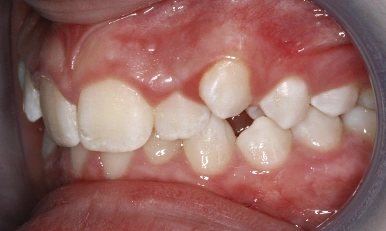

Patient Results